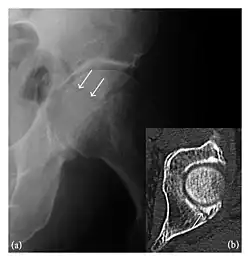

Occult osseous injuries may result from a direct blow to the bone by compressive forces of adjacent bones against one another or by traction forces during an avulsion injury. Lesions in the tibial plateau, hip, ankle, and wrist are often missed. In a tibial plateau fracture, any disruption of the posterior and anterior cortical rims of the plateau should be sought. Impaction of subchondral bone will appear as an increased sclerosis of the subchondral bone (Figure 1). In the hip, posterior acetabular fractures also present subtle radiographic findings. The acetabular lines should then be carefully examined keeping in mind that the posterior rim, which is harder to see on X-rays, is more frequently fractured than the anterior rim (Figure 2). In the wrist, detection of carpal bone fractures is often challenging, with up to 18% of scaphoid fractures radiographically occult. Carpal fractures, especially the scaphoid, are associated with the risk of avascular necrosis. In apparently normal wrist radiographs from symptomatic patients, if there is history of a fall on an outstretched hand with pain in the anatomic snuffbox, suggesting scaphoid injury, the initial examination with posteroanterior, lateral, and pronation oblique views must be complemented by other specific views such as supination oblique and the "scaphoid" view A careful examination of cortices for evidence of discontinuity or offset and cancellous bone for lucency is necessary (Figure 3).[1]

Figure 4: Dorsal triquetral fracture of the left wrist in a 30-year-old man after a trauma. (a) Anteroposterior radiograph shows a normal appearance. (b) Lateral radiograph of the same wrist demonstrates a chip fracture off the dorsal aspect of the triquetrum (arrow).[1]